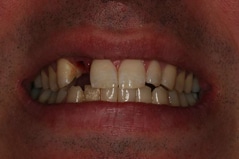

Anthony A.

This patient had only a few remaining infected teeth, but didn’t want to settle for just a denture.  Placed multiple implants and provided a secure fixed option which allowed him to not only chew better but to smile again.